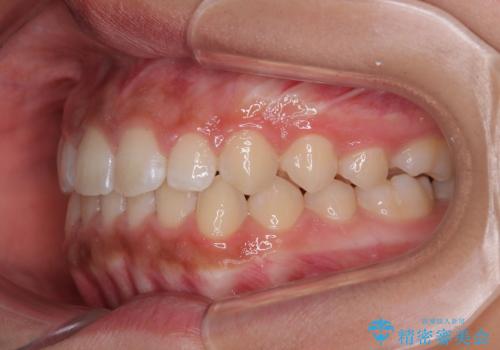

気になるすきっ歯を短期間で改善 インビザライン矯正

- 前歯の隙間を気にして来院された患者様です。

口元の突出感があり、小臼歯4本を抜歯して口元を引っ込める矯正治療も提案しましたが、本人は口元の突出感は気になっていないとのことで、インビザラインにて隙間やデコボコを改善することとしました。

軽度の歯列不正であったため、廉価版のインビザライン・モデレートパッケージにて治療を終えることができました。